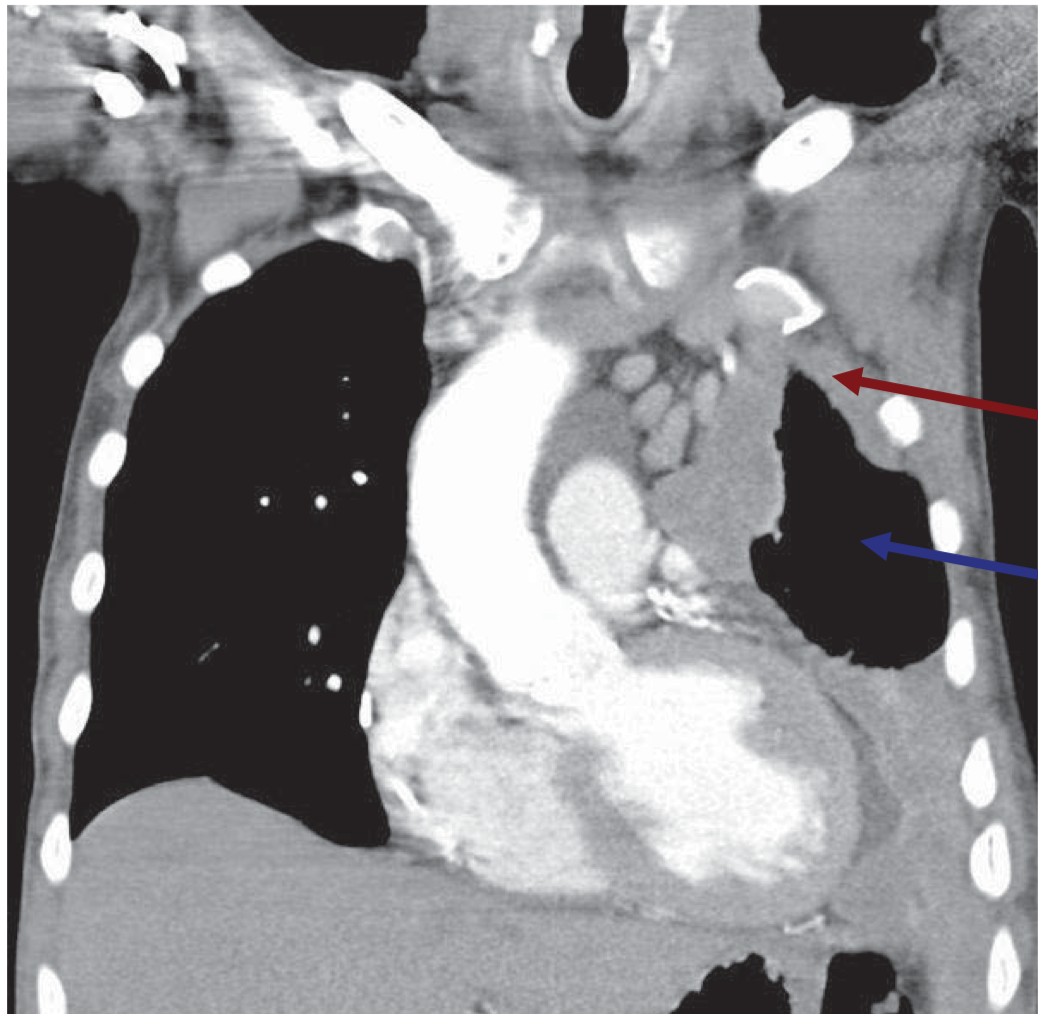

What is your Dx?

Idiopathic pulmonary fibrosis (honeycomb appearance)